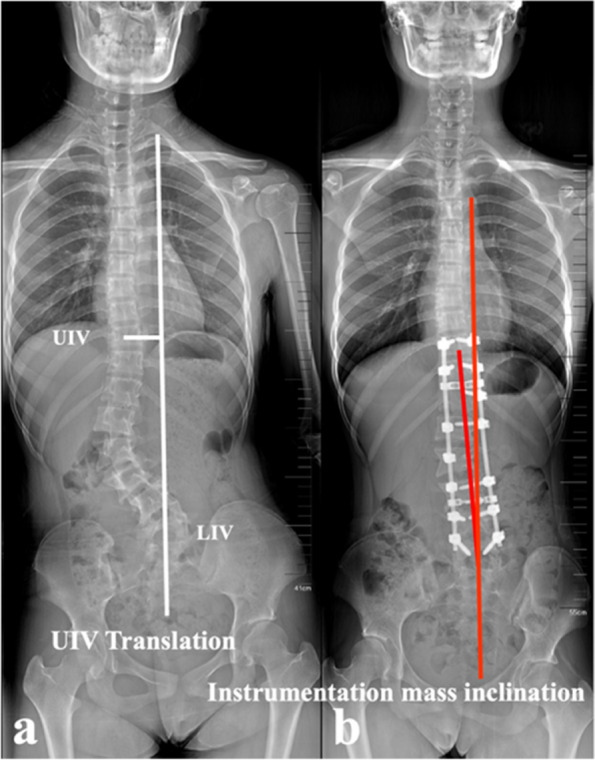

Radiographic parameters were measured pre- and post-operatively for analysis of CCI prognosis, involving main curve Cobb angle, CBD, UIV (upper instrumented vertebra) tilt, LIV (lower instrumented vertebra) tilt, UIV translation and instrumentation mass inclination. All measurements were performed using the Surgimap spine software (Version 2.3.1.5; Spine Software, New York, NY). The definitions of the standard measuring techniques of the aforementioned parameters were defined as follows:

- UIV tilt: defined as the angle formed by the line drawn parallel to the superior end plate of the UIV and the horizontal line. A positive value was defined as the UIV inclining to the convexity of the main curve.

- LIV tilt: defined as the angle formed by the line drawn parallel to the superior end plate of the LIV and the horizontal line. A positive value was defined as the LIV inclining to the convexity of the main curve.

- UIV translation (Fig. 4a): defined as the distance from the center of UIV to the CSVL. A positive value was defined as the UIV translating to the convexity of the main curve.

- Instrumentation mass inclination (Fig. 4b): defined by the angle formed between the line drawn from the center of UIV to the center of LIV and the vertical line. A positive value was defined as the instrumentation mass inclining to the convexity of the main curve.